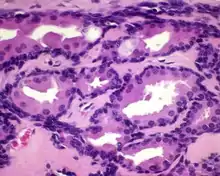

All of the tumors are unencapsulated, but are usually well defined or circumscribed. The overlying surface epithelium is not involved. The tumor shows a dual or biphasic appearance, with glandular or cystic spaces showing inner luminal secretory cells with abundant granular, eosinophilic cytoplasm subtended by basal, myoepithelial cells at the periphery, adjacent to the basement membrane. The luminal cells will often have decapitation (apocrine) secretions and will also have yellow-brown, ceroid, lipofuscin-like (cerumen) pigment granules. There is no pleomorphic, limited mitoses, and no necrosis.[2]

Immunohistochemistry can be performed to confirm the biphasic nature of the tumor. All cells are positive with pancytokeratin and epithelial membrane antigen; only the luminal cells are positive with CK7; only the basal cells are positive with CK5/6, p63, S100 protein. CD117 can be positive in either population. The cells are negative with chromogranin, synaptophysin and CK20.[2]